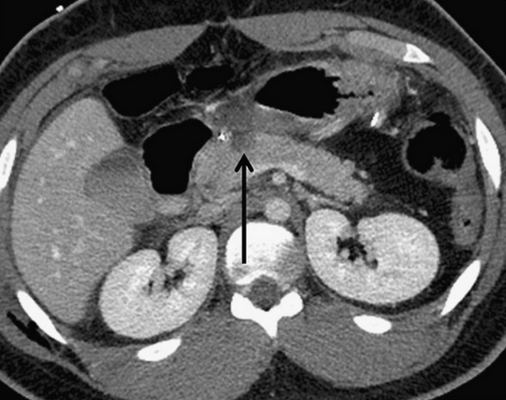

На КТ поджелудочной железы при травмах OIS I и II степени проявляются слабо контурирующие «потухшие» участки на фоне нормальной паренхимы или очаговое или диффузное расширение поджелудочной железы. Незначительная контузия (I степень) (изображение 1) включает одну анатомическую область поджелудочной железы, при II степени травмы (изображение 2) задействуется более одной анатомической области поджелудочной железы.

Изображение 1. Сорокадвухлетний мужчина с травмой поджелудочной железы. Изображение показывает небольшую гиподенсную область в передней части головки поджелудочной железы (стрелка), указывая на травму I степени.